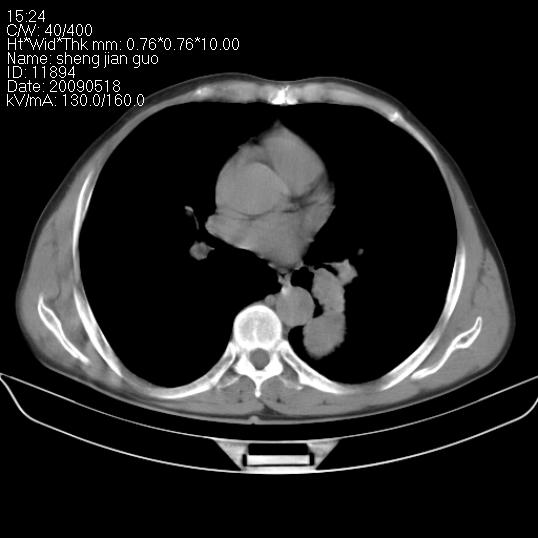

以下是引用zjzjr在2009-5-19 17:25:00的发言:[br]支持楼主考虑,另左肺下叶阻塞性炎症。

以下是引用zhao_bin2008在2009-5-19 17:48:00的发言:[br]支持左肺下叶周围型肺癌并阻塞性肺炎。

以下是引用杀毒软件在2009-5-19 17:36:00的发言:[br]支持楼主

以下是引用zsl6918在2009-5-20 7:10:00的发言:[br]左侧中心型肺癌!